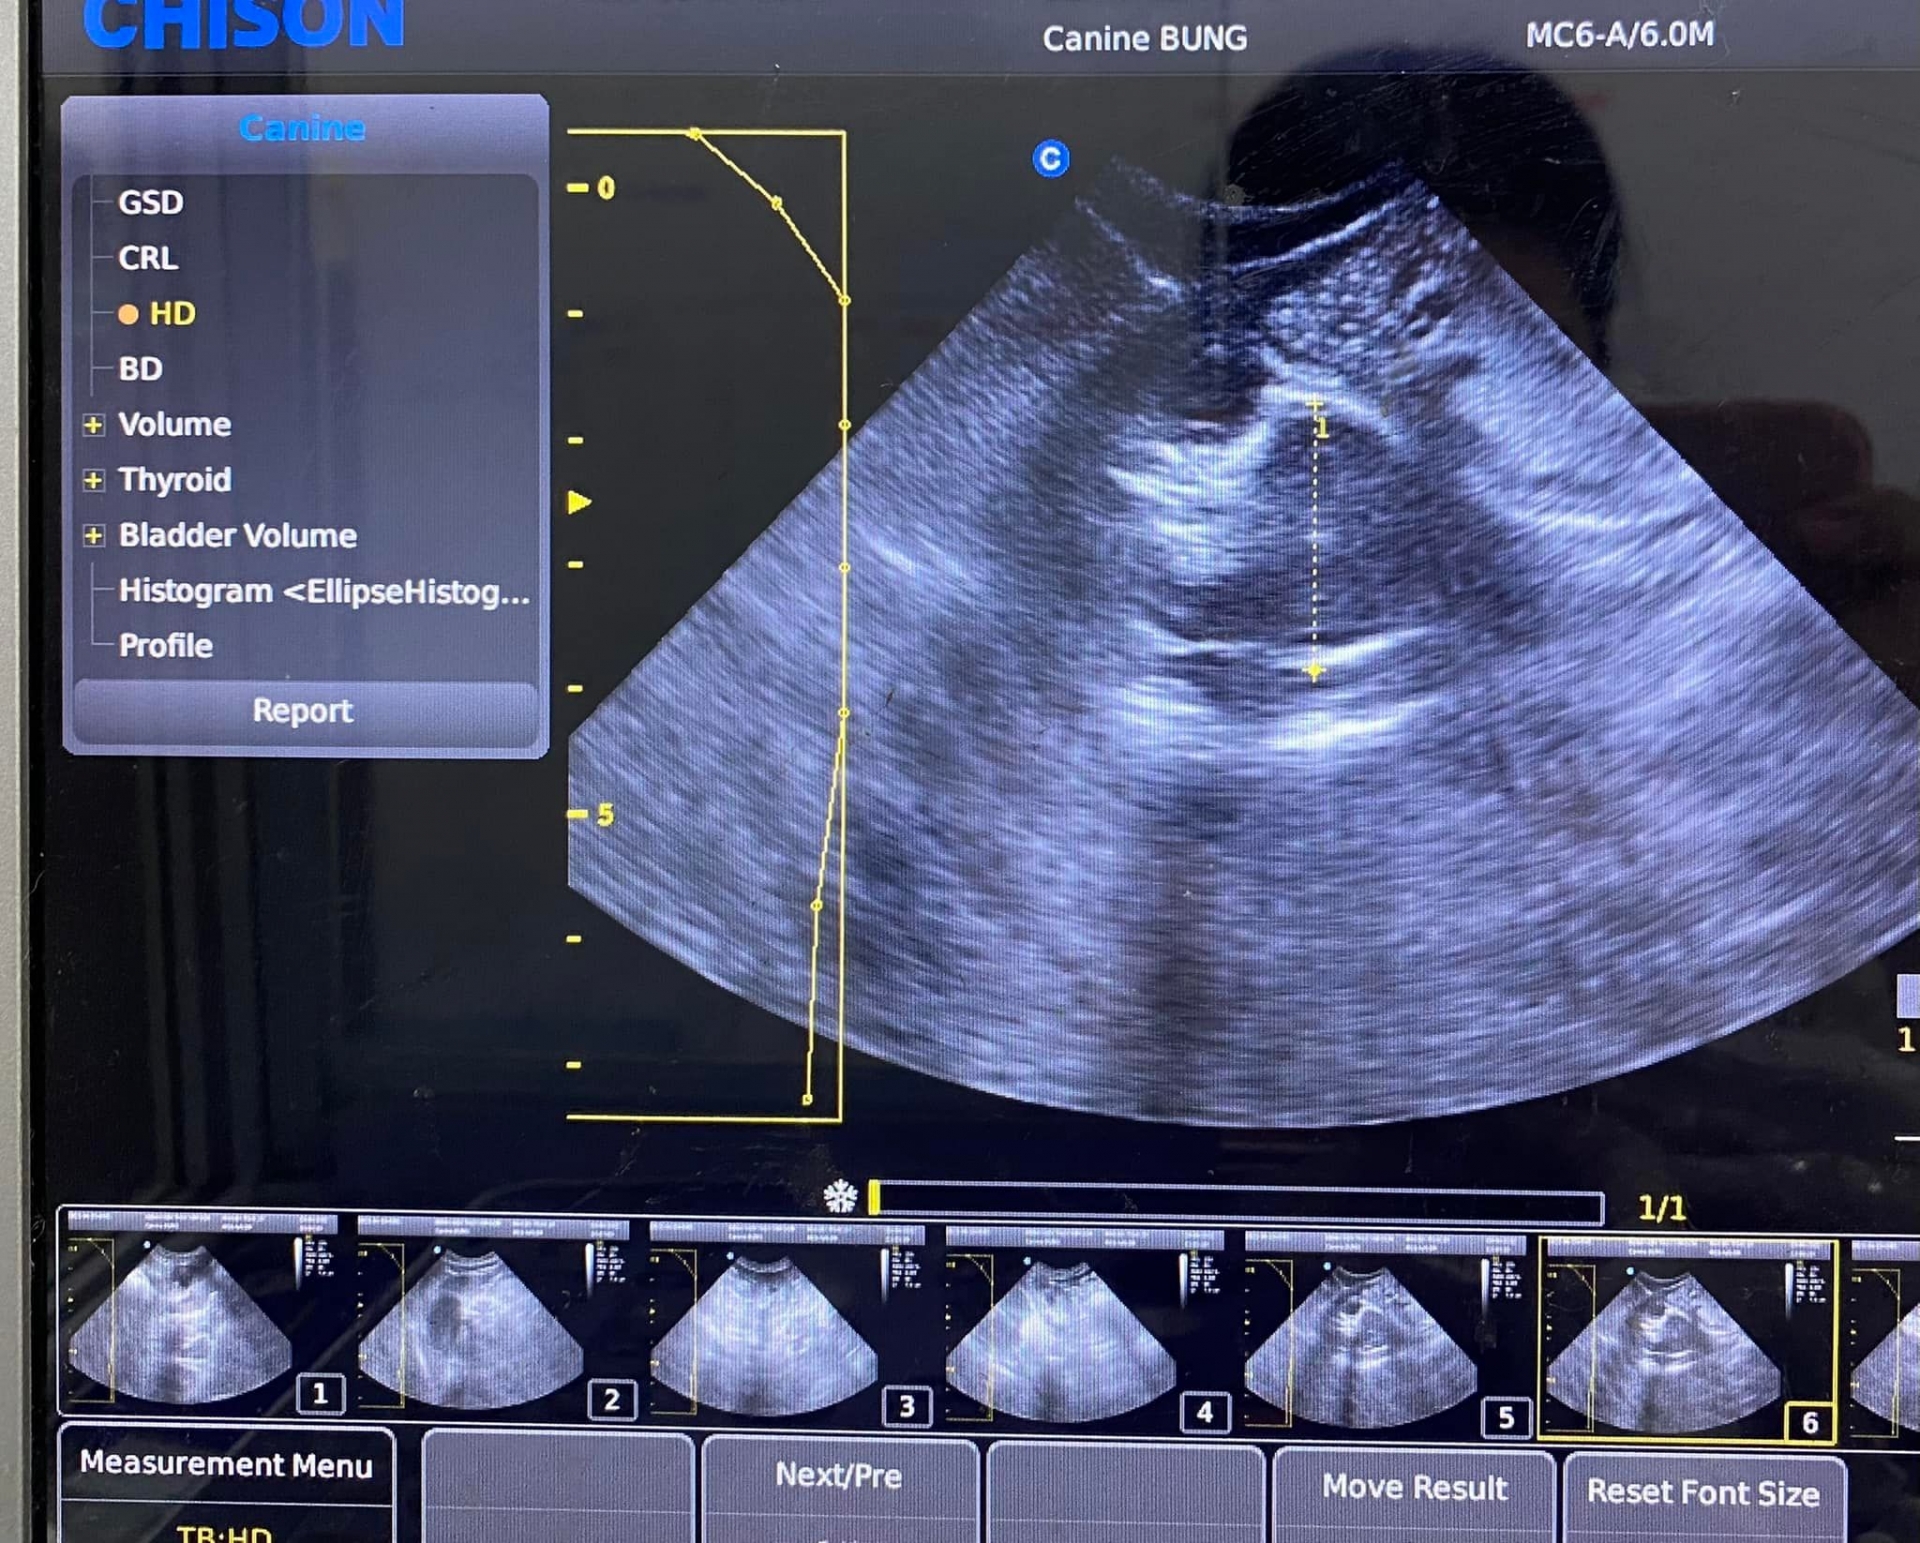

Ngoài ra, khi được hỏi về bức ảnh siêu âm đăng tải trên trang cá nhân vài ngày trước, nữ diễn viên phủ nhận tin đồn mang thai lần 3. Cô vui vẻ cho biết đó chỉ là ảnh siêu âm của chú mèo cưng, không có chuyện gia đình có thêm thành viên mới.